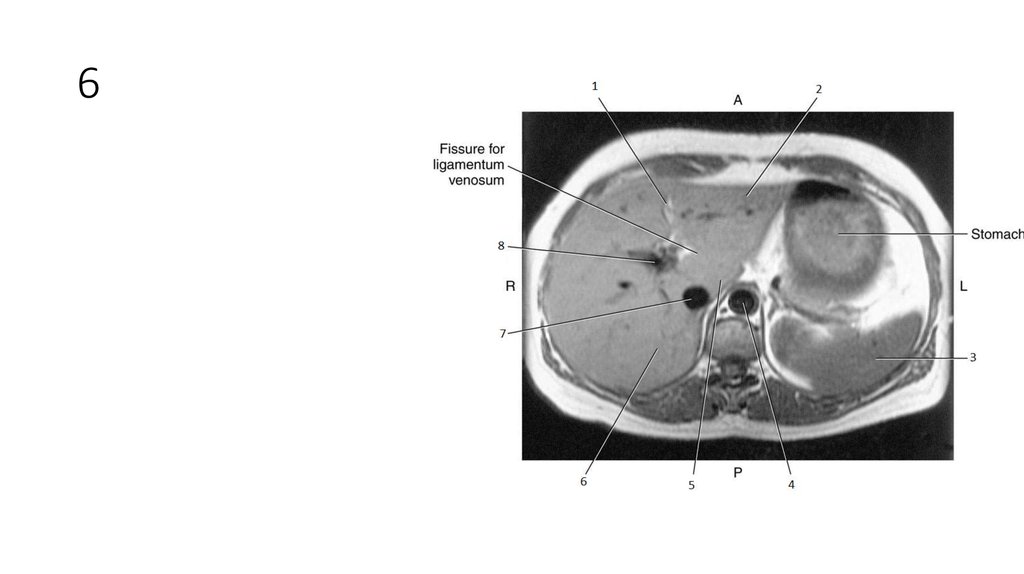

26. 6

27. 6

• Right Lobe of Liver